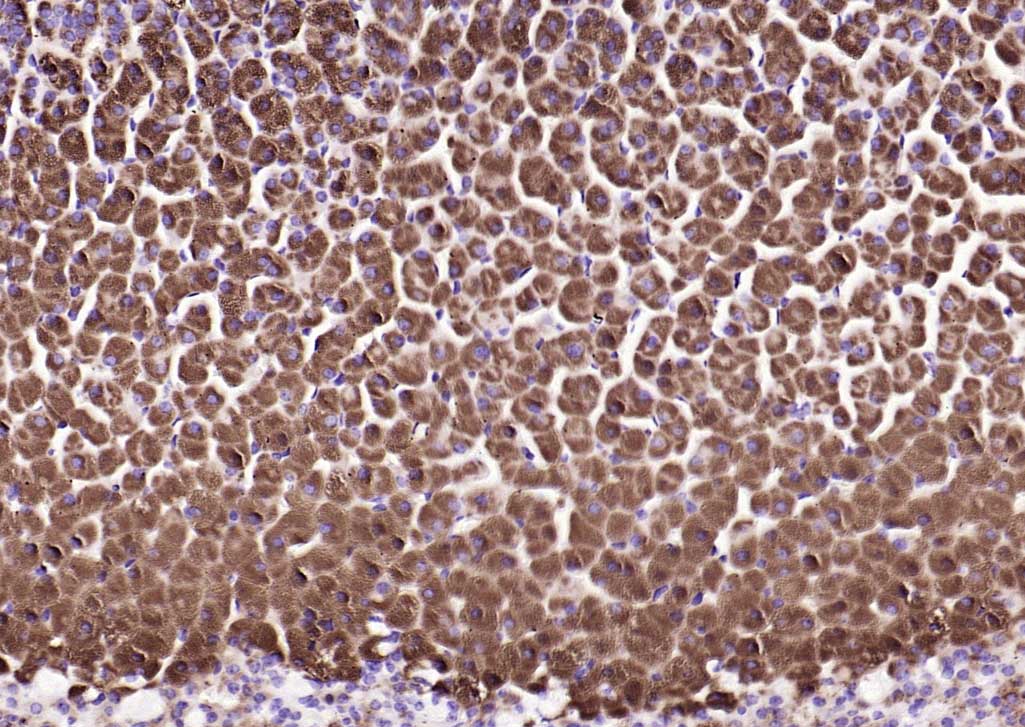

| IHC-P | Human, Mouse, Rat | Dog, Horse | 1:100-500 |